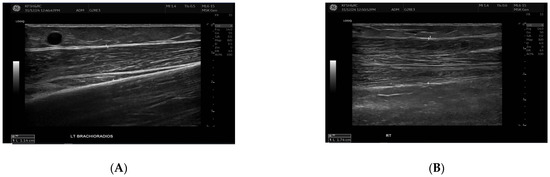

Figure 2.

This figure demonstrates the comparison of brachioradialis muscle thickness between the fistula (A) and the contralateral arm (B). B-mode ultrasound images showing brachioradialis muscle thickness measurements. The left panel (A) (fistula side) demonstrates reduced muscle thickness (1.14 cm) compared with the contralateral arm (right panel (B), 1.74 cm). Measurements were obtained in the mid-muscle belly using a linear high-frequency transducer.